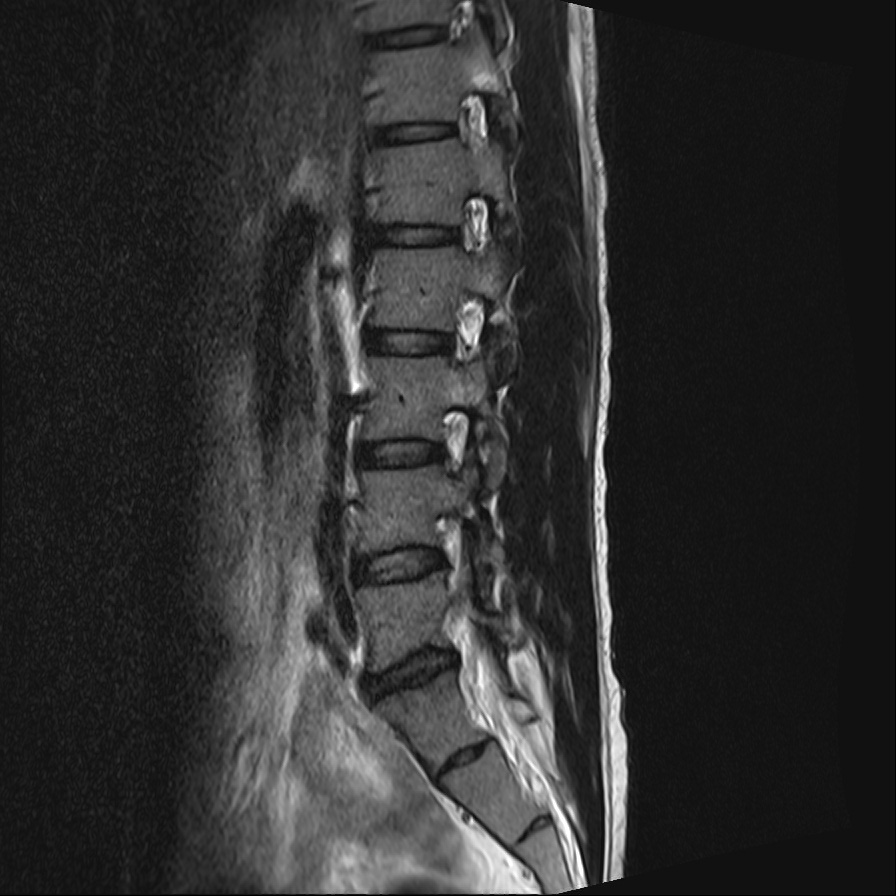

My spinal cord including bones and discs.

My spinal cord. Discs only.

On September 1st, 2022, I took an MRI of my spinal cord. The doctor showed me my spinal cord on the screen and gave me the MRI scan on CD. Then I met Dr. Marianne Black on January 11th 2023. She showed me a musculoskeletal 3D model she had created based on an MRI scan. Her works are very inspiring and motivated me to work on this.